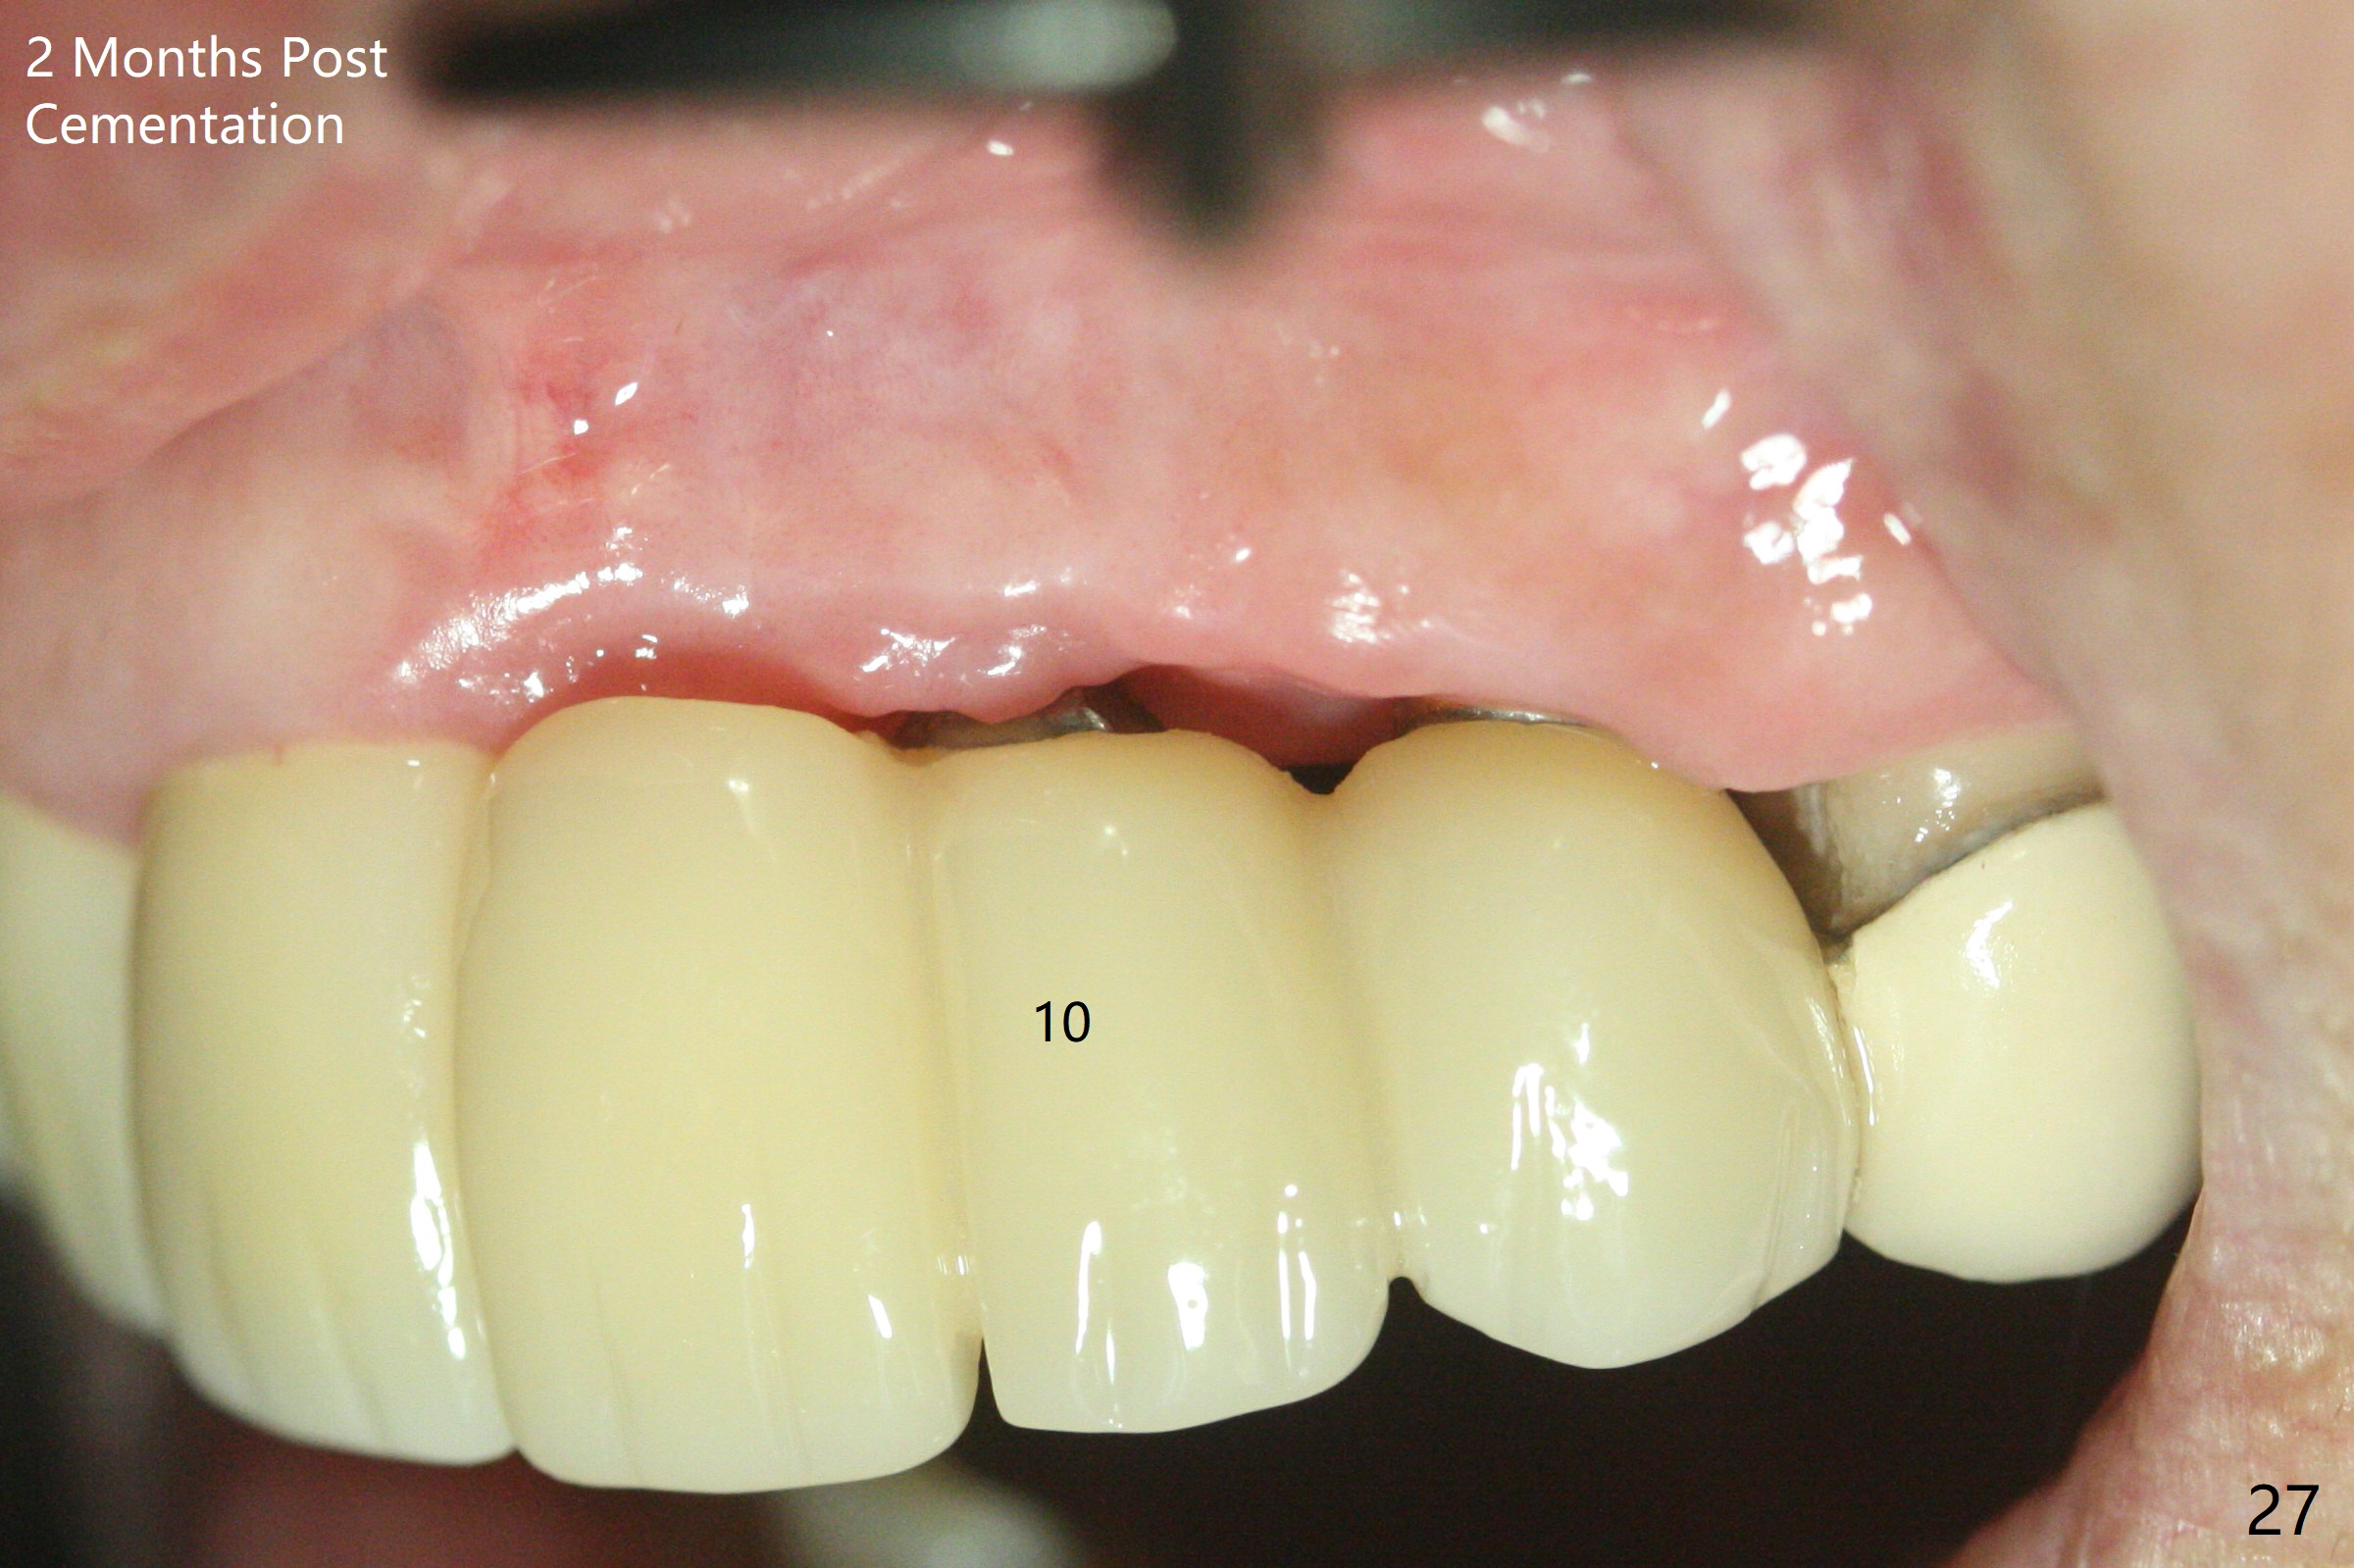

The mesiobuccal margin at #8 is redefined 4 weeks postop (Fig.14) so that the cervical end of the temporary crown is able to move mesially (Fig.13). The most coronal portion of the bone graft at #11 begins to be detached (*). The mesial portion of the abutment at #10 will be removed (curved white line) in the following week. After removing the most coronal portion of detaching bone graft at #11, acrylic is added to form a concave pontic (Fig.15 ^). With removal of the mesial portion of the abutment at #10, the retainer is moved distal (>). Pontics form at UL1 and 3 two months postop (Fig.16 *), while there is buccal atrophy at UL1,2 (Fig.17). 术后3个月植牙区牙龈形态良好(图十八),即将暴露,放置愈合基台。图十九是在右上1根管治疗时(基台放置后五天)拍摄。左上3术后3个月3个星期,1,2唇侧塌陷(图二十)。叶状植体处牙槽嵴往根尖萎缩(图二十一:^)。尽管做了松弛切口,放入事先预备的粘性骨粉后,几乎没有空间放置结缔组织移植物,恰好还没有取。放置PRF膜后,使用4-0 Monoglyc缝线缝合。牙龈似乎冠方移位(图二十二:箭头)。植骨后,唇侧仿佛饱满多了(图二十三:*)。骨粉放置于左上1,2唇侧和牙槽嵴(图二十四:*,与之前(图十九)对比)。后者有助于牙龈冠方移位,而前者有助于增加唇侧饱满度。植骨术后两周唇侧仍饱满(图二十五,六)。植骨后四个月牙冠粘固,两个月后,病人抱怨10号牙左右食物坎塞(图二十七),9/10牙冠撤除,10基台边缘加深,重做临时牙冠,同时增加9凹陷(pontic)。一个月后,9/10临时牙冠修整两次,11永久性牙冠撤除,也制备临时牙冠,外形明显改善(图二十八)。